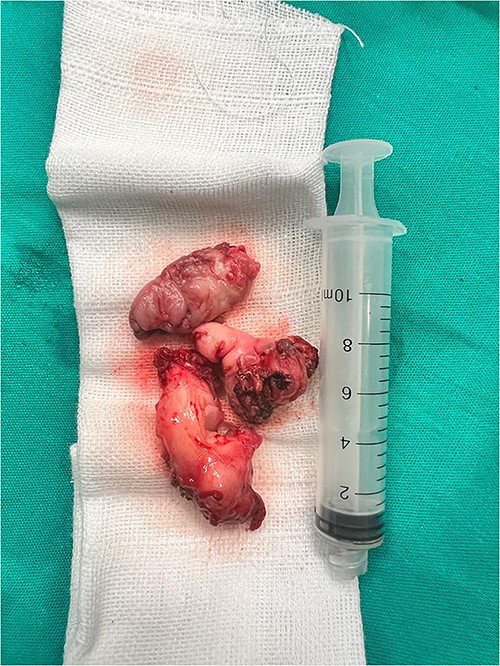

A 63-year-old male presented with a 1-year history of dysphonia, hoarseness, choking, progressive dysphagia, and a sensation of throat obstruction. The patient, a smoker, denied cough and weight loss. Family history was unremarkable. Physical examination revealed no specific features, and there was no evidence of lymphadenopathy or distant metastasis. The strobolaryngoscopy was performed and a mass above the left vocal cord was identified (Fig. 1) (Video S1). The mass was completely resected using micro scissors under general anesthesia, with visualization using a microscope attached to the laryngoscope, and was subjected to pathologic examination. A gross examination of the resected mass revealed multiple fragments measuring 7 cm in maximum diameter (Fig. 2). Microscopically, there was diffuse and nodular proliferation of bland fusiform or stellate neoplastic cells in a myxoid stroma (Fig. 3A). The fibrotic areas are more cellular but the cells themselves appear similar to those in the myxoid areas (Fig. 3B). Tumor cells have small hyperchromatic nuclei (Fig. 3C and D). Mitotic figures are rare. In immunohistochemistry, cytokeratin is negative (Fig. 4A). Ki67 rate is very low (Fig. 4B and C). Tumor cells show positivity to vimentin (Fig. 4D). The diagnosis of LGFMS was made. After a follow-up period of 6 months, the patient had no signs of tumor recurrence or metastases, as confirmed by a computed tomography (CT) scan (Fig. 5).

The gross image of the mass shows multiple fragments, all measuring 7 cm.